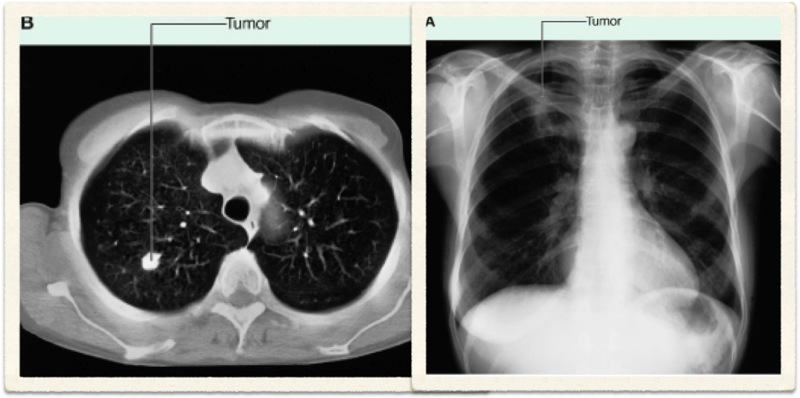

Radiological Report: Cardiac size within normal limits. Both lungs show severe overinflation typical of COPD. No sign of mass or consolidation.

Hyperinflation secondary to emphysema

Chronic bronchitis cannot be diagnosed radiologically. Although findings such as increased lung markings or tubular opacities, bronchial wall cuffing (thickening) can be seen with bronchitis, they are nonspecific. The main reason for getting a chest X-ray is to exclude other conditions, such as bronchiectasis, which can mimic the disease clinically.